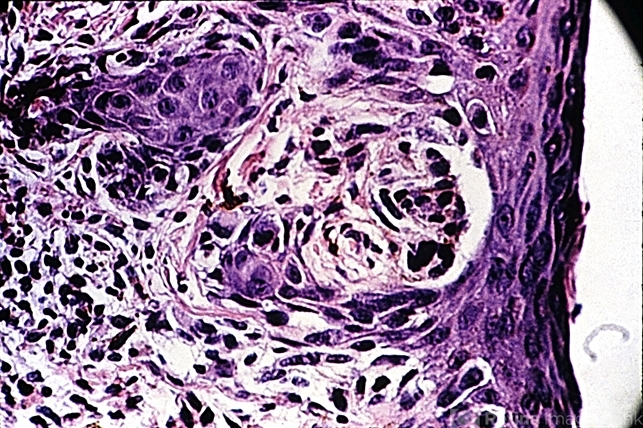

- melanocytes, junctional nevus, melanoma

- Nest of atypical melanocytes resembling a junctional nevus at the edge of a superficial spreading melanoma in a 70-year-old female. Note the inflammatory cells in the dermis.